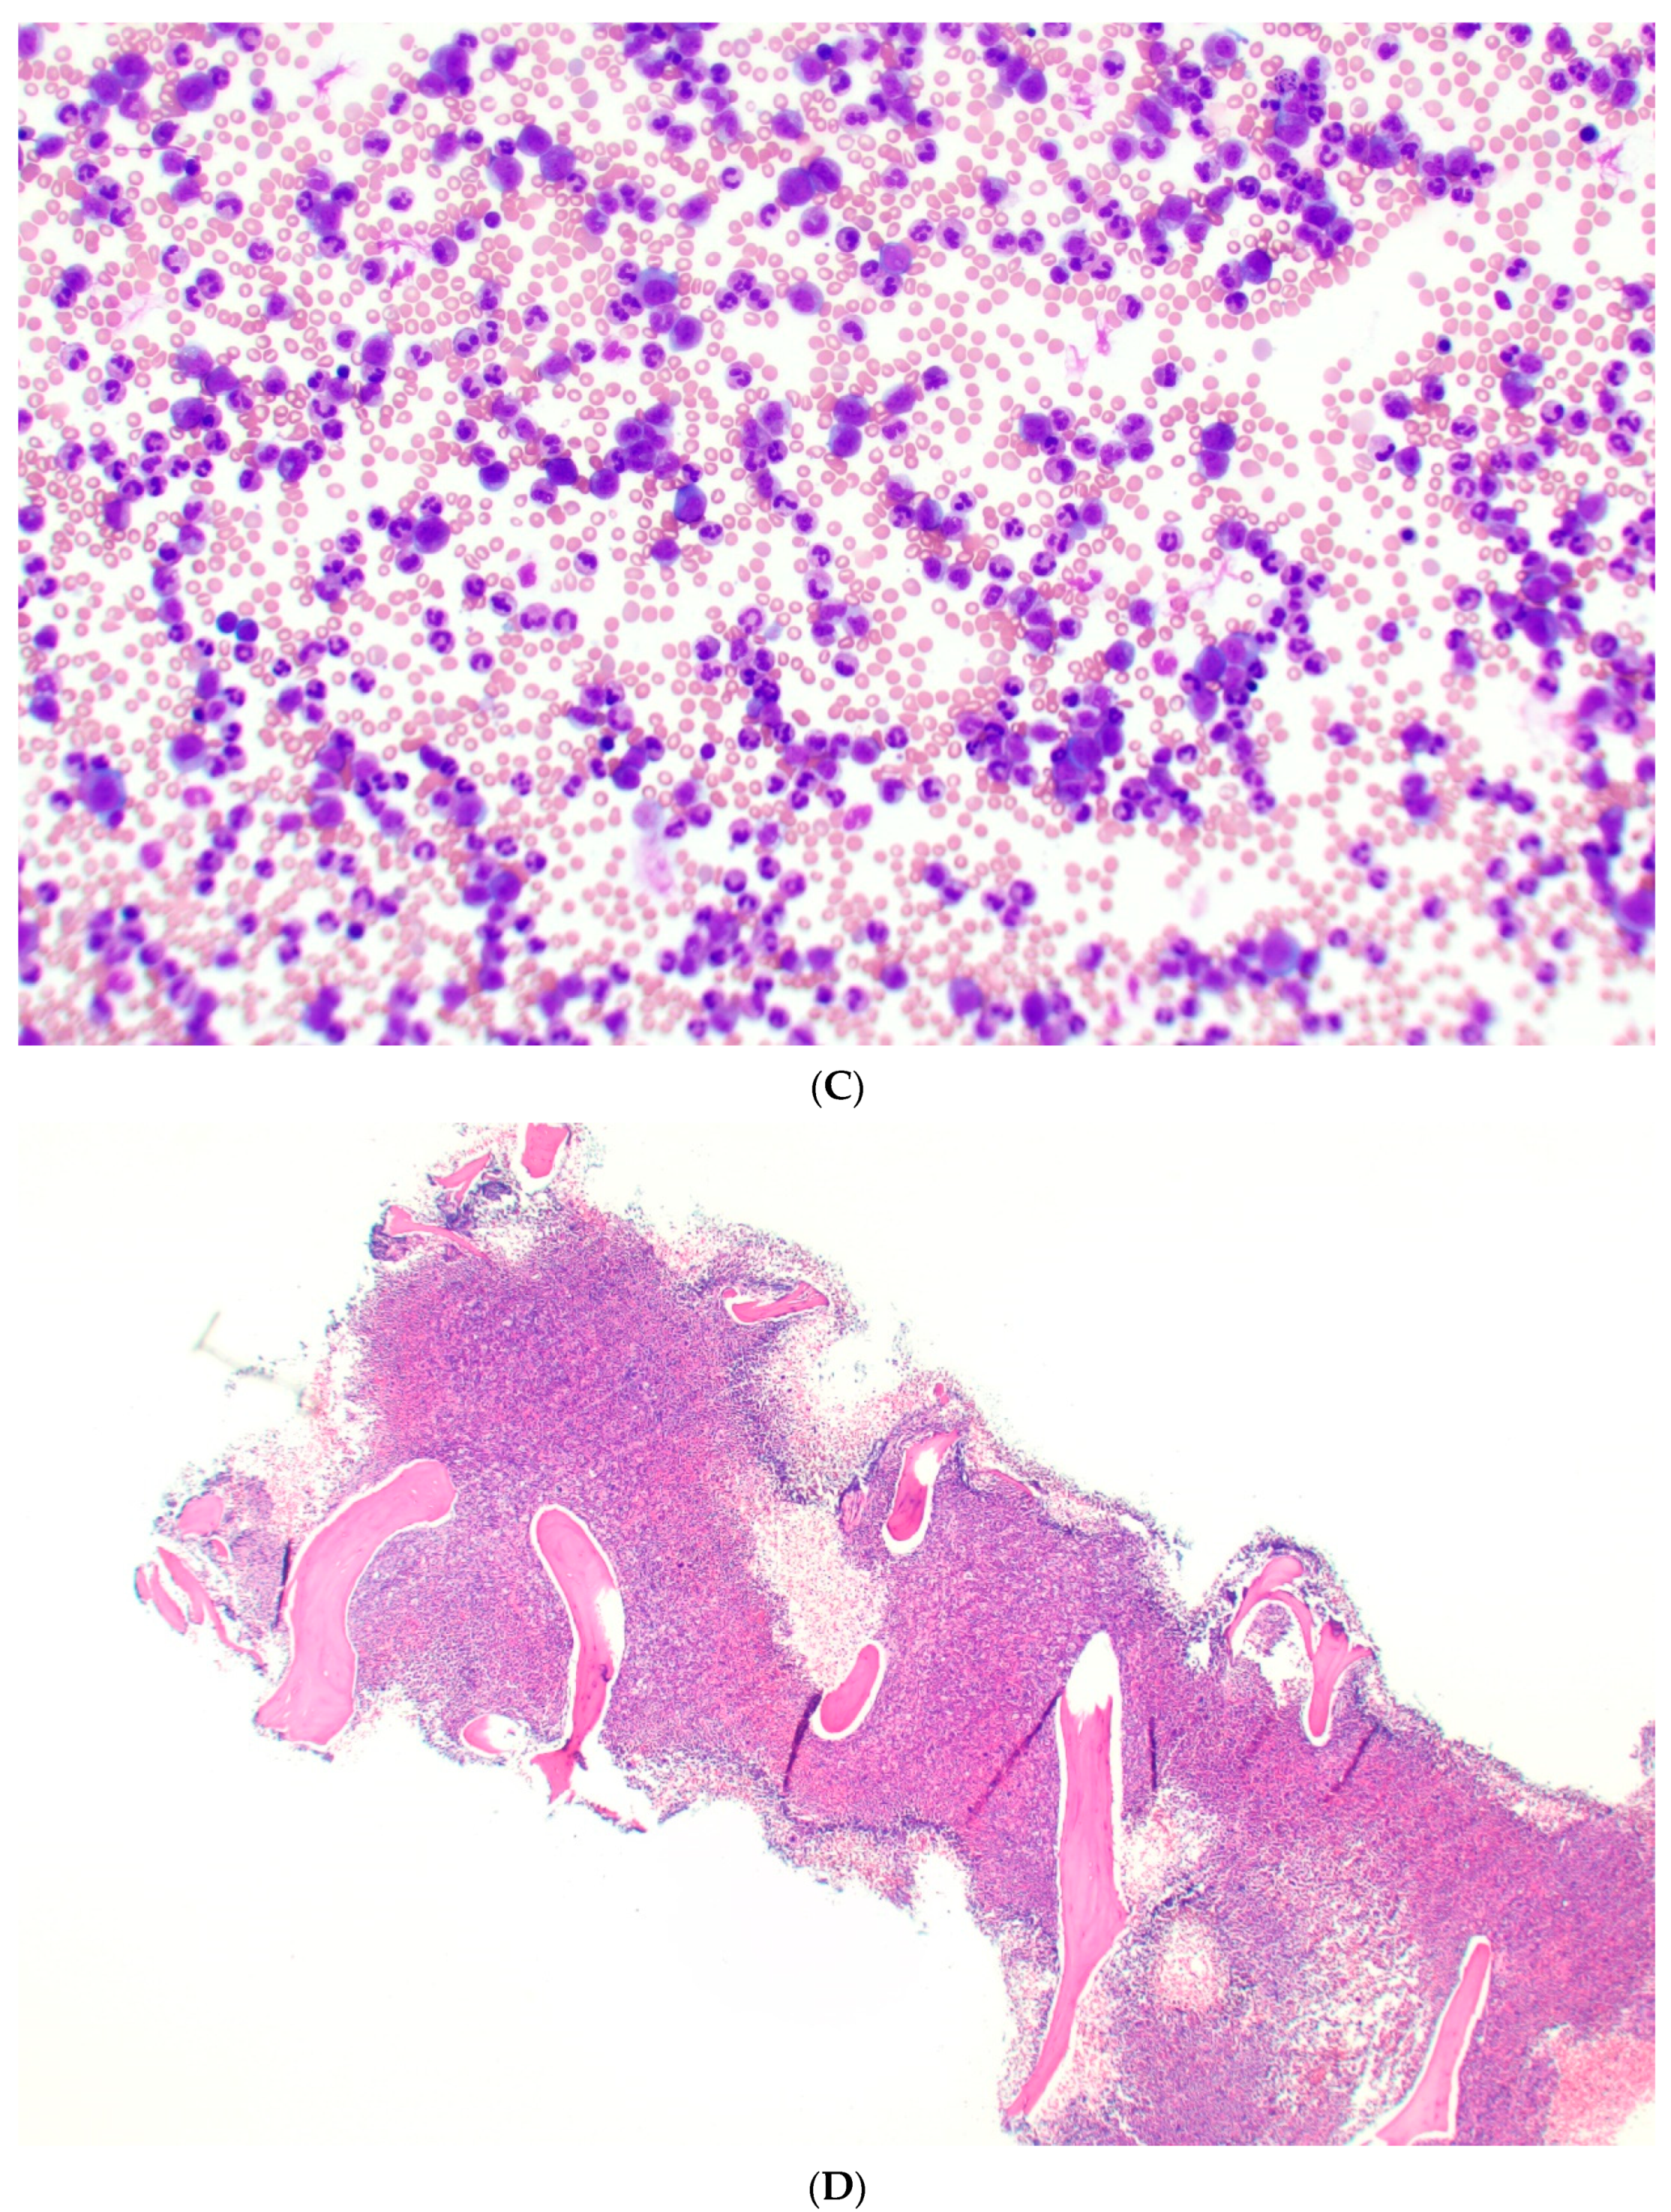

3.2.2. Bone Marrow

4. Cytogenetic and Molecular Characteristics